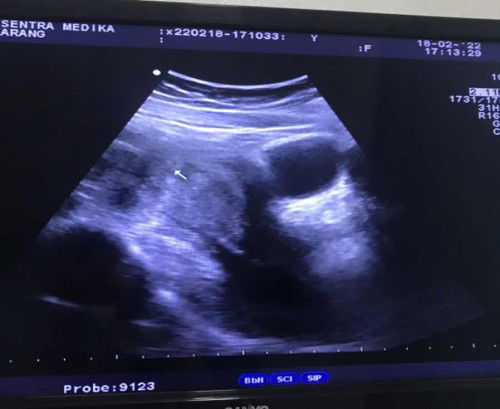

Halo bunda semua.. mau tanya, aku USG 4 weeks tapi kata dokternya masih penebalan rahim, apakah itu normal? Insya Allah besok tanggal 12 maret mau kontrol USG ke 2 di usia 8 weeks.. apakah diusia segitu biasanya udah keliatan janin & djj ya? Selama ini aku ga ngerasain ngeflek, makan apa aja masuk, mual jarang2 banget paling pagi doang itu juga cuma bbrp kali.. ditambah aktifitas yg lumayan, berhubung sama suami sama2 kerja, beda perusahaan, dia kena shift aku non shift jadinya pp naik motor masing2.. pekerjaan rumah pun dibagi 2 jadi aku ttp kerjain kerjaan rumah sebagaimana mestinya. Apa ada yg sama kyk aku? & gimana kondisi kandungannya? Mohon saran & jawabannya ya bund🙏🏻❤️ #ingintahu #pleasehelp #firstbaby #mohonbantu #7week2day #tanyabidan